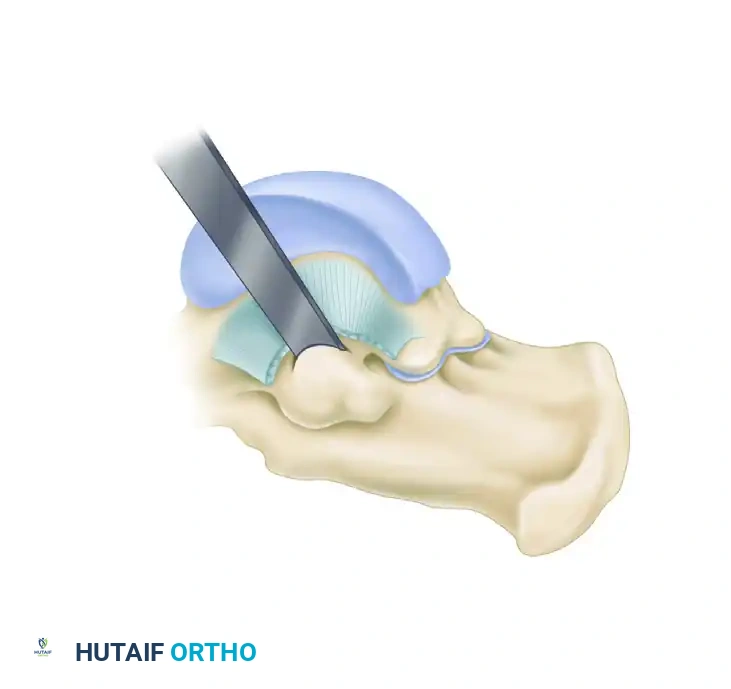

3. Superficial Dissection and Tendon Management

- Incise the skin and subcutaneous tissue. Carefully manage and ligate any large superficial veins to prevent postoperative hematoma.

- Palpate the sustentaculum tali, located approximately 2 cm plantarward and slightly distal from the tip of the medial malleolus.

- Identify the flexor digitorum longus (FDL) tendon, which passes directly over the central portion of the coalition.

- Open the FDL tendon sheath longitudinally. Mobilize the tendon and retract it either dorsally or plantarly to expose the underlying osseous pathology.

FIGURE 82-85 A: Surgical exposure for resection of a middle facet tarsal coalition. The FDL sheath is opened, and the tendon is retracted to expose the underlying coalition at the sustentaculum tali.

4. Exposure of the Coalition

- Incise the periosteum directly over the coalition. Use a periosteal elevator to define the proximal, distal, dorsal, and plantar margins of the coalition mass.

- Expose the entire coalition and a limited, safe area of the normal posterior facet to serve as a visual landmark. This helps avoid inadvertent injury to the normal articular cartilage with the osteotome.

- Identify the flexor hallucis longus (FHL) tendon at the plantar margin of the coalition. The coalition sits directly over the FHL; retracting the FHL plantarly protects it during the bony resection.